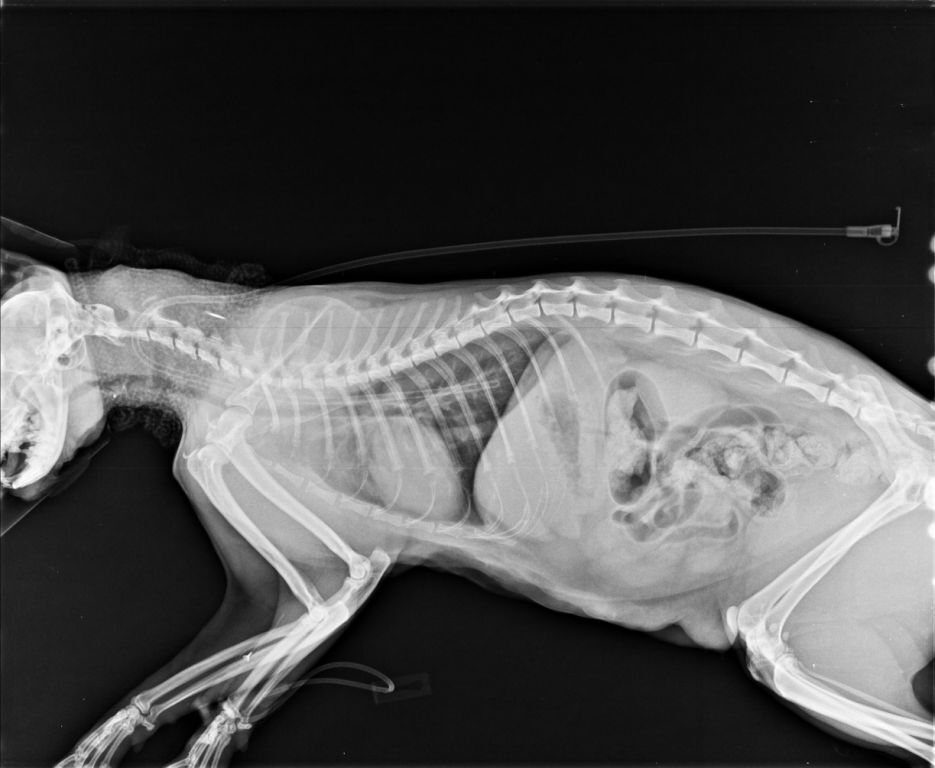

白親親於住院期間由於嚴重的口水不止以及鼻塞導致張口呼吸

不吃不喝因此院方替白親親裝設食道胃管

治療後逐漸穩定而出院